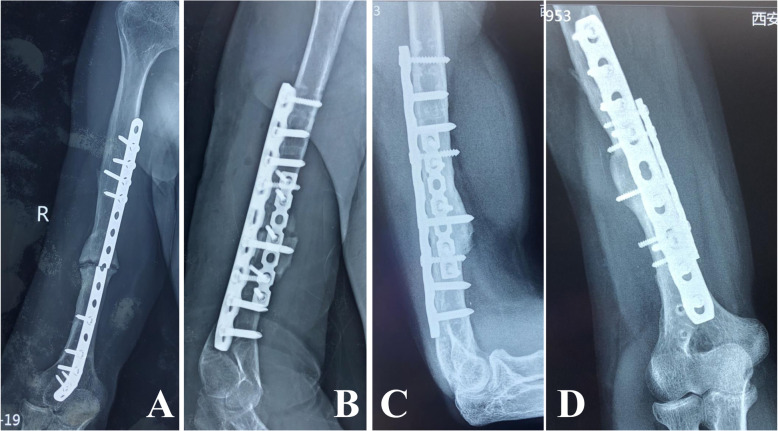

Images from a 42-year-old man with right humeral shaft nonunion for more than 26 years who had undergone four surgeries before seeking treatment at our institution. a Radiograph showing nonunion with implant failure at 4 years after the last revision. b Fixation using double locking compression plating and bone grafting. c, d Radiographs demonstrating osseous union at 8 months postoperatively